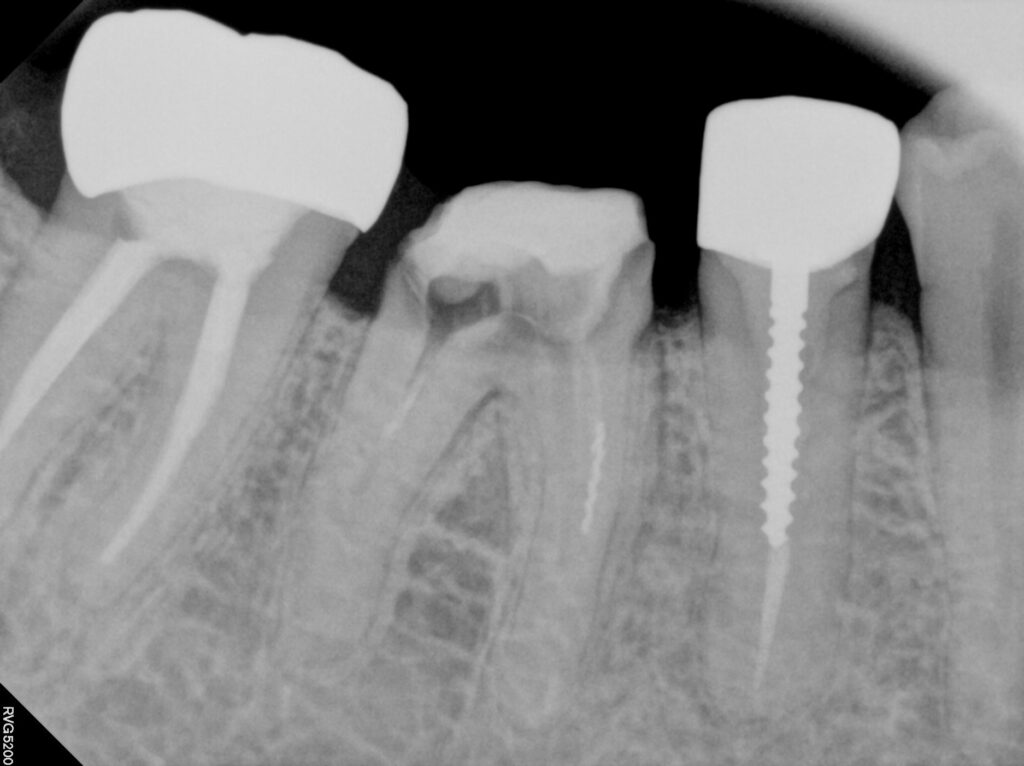

25.05 최oo님

구강안을 살펴보니 치아의 머리에 해당하는

크라운 부분이 전부 없는 상태였습니다.

우선 이 치아를 살릴 수 있는지

여부부터 파악해야 했는데요.

이 환자분의 경우

남아있는 치질량만 봤을 때는 발치가능성을

배제할 수는 없었습니다.

신경치료 및 코어작업까지

깔끔하게 마무리 된 상태입니다.